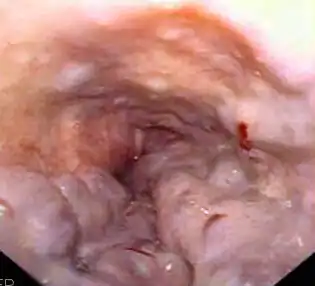

El diagnóstico se establece por medio de una esofagogastroduodenoscopia, la cual debe ser realizada en todo paciente con hemorragias idiopáticas, cirrosis o esplenomegalia y con carácter de urgencia si presentan sangrado digestivo masivo. Las varices se presentan de color azul, redondeadas y compresibles, haciendo prominencia en la mucosa del esófago. La ventaja de este diagnóstico directo es poder saber su posición, tamaño y otros signos como manchas rojas brillantes que indiquen un inminente sangrado o coágulos de sangre donde haya existido una hemorragia.